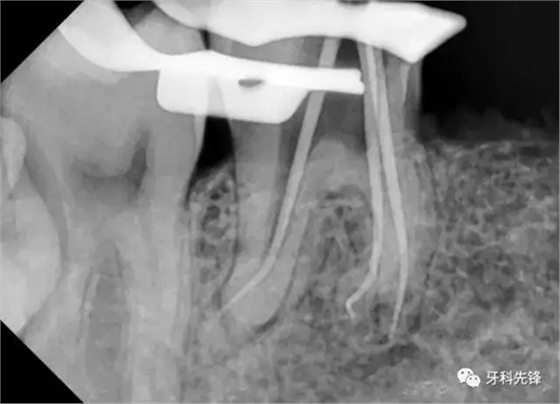

處置: 46右下牙槽神經(jīng)阻滯麻醉,46橡皮障隔濕,去凈腐質,開髓,拔髓,GG鉆擴大根管口,根管疏通,根測,ML=19.5mm,MB=18mm,DB=DL=18mm,EDTA作用下M2鎳鈦機擴至25#,試尖拍片,干燥根管,AHplus糊劑+牙塞尖+熱牙膠加壓根充,,聚羧酸鋅墊底,Z350納米樹脂充填,調合,拋光。